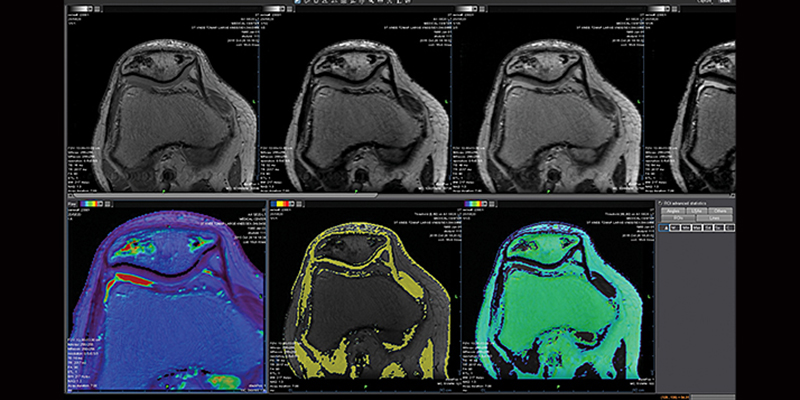

Клінічний пакет MR Ortho Expert

Пакет MR Ortho Expert, що розроблений Olea Medical, включає спеціалізовані рішення для експертних користувачів, які хочуть отримати доступ до найновіших інструментів та програм для ортопедичної візуалізації.

Програмний пакет Relaxometry

Додаток Релаксометрія вимірює час релаксації за МРТ-зображеннями, покращує чутливість та знижує суб’єктивність візуальної оцінки, таким чином, покращуючи дослідження аномалій тканин.

За допомогою цього плагіна фахівці можуть оцінити розподіл води в хрящі для кращого виявлення суглобових аномалій, таких як ранній остеоартрит.

Плагін також дозволяє фахівцям вимірювати зміни хрящів у спортсменів, на яких часто впливає передчасне старіння та травми. Плагін релаксометрії надає T2_map, обчислену з T2-послідовностей (спінові ехо-послідовності з декількома ехо), пропонуючи оцінку T2.

Пакет MSK Cartilage

Додаток для оцінки хряща MSK (склетно-м’язовий пакет) створено для лікарів для візуальної оцінки пошкоджень хряща. Додаток MSK поєднує програми аналізу та релаксометрії.